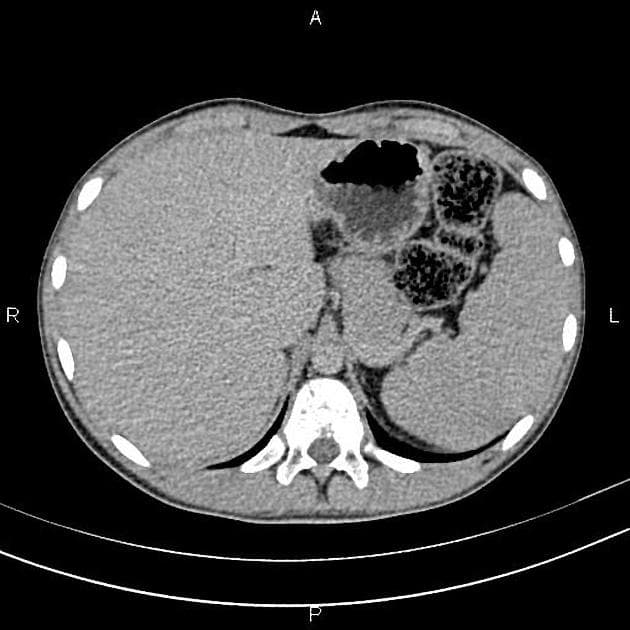

Vùng bụng - chậu

thận (~70% bệnh nhân 10,17)

nang thận

gặp ở tới 75% bệnh nhân 5

thường có khuynh hướng hai bên và nhiều nang

có thể là nang đơn giản, nang phức tạp hoặc ung thư biểu mô tế bào thận dạng nang 10

tụy (có thể là biểu hiện sớm nhất 3)

nang tụy: ~40% bệnh nhân 10

khối u thần kinh nội tiết tụy (pNET)

~12,5% bệnh nhân (khoảng 9-17%) 10

thường không có chức năng 9

thường gặp nhiều tổn thương

u nang tuyến thanh mạc tụy: ~12,5% bệnh nhân (khoảng 9-17%)

gan

nang gan